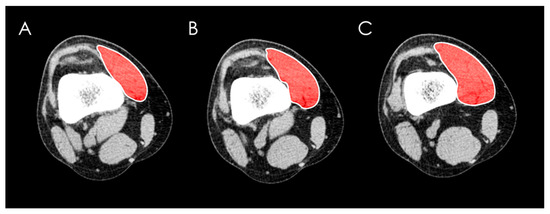

13 pages, 5802 KB

Tendon Yaw (TY) Angle: Direct Measurement of the Quadriceps Vector Resolves the Rotational Enigma of Recurrent Patellar Instability

Background and Objectives: To validate a computed tomography (CT) measure of tendon yaw (TY) and determine its diagnostic specificity, precision, and clinical relevance in recurrent patellar instability (RPI) in comparison with standard imaging tests (SIT1, SIT2), femoral trochlear dysplasia (FTD), and vastus [...] Read more.

Background and Objectives: To validate a computed tomography (CT) measure of tendon yaw (TY) and determine its diagnostic specificity, precision, and clinical relevance in recurrent patellar instability (RPI) in comparison with standard imaging tests (SIT1, SIT2), femoral trochlear dysplasia (FTD), and vastus medialis obliquus (VMO) morphology. Materials and Methods: This retrospective cross-sectional study included 113 subjects (187 knees) examined using a standardized CT protocol for RPI following strict exclusion criteria. TY, SIT1, and SIT2 were measured using predefined axial landmarks. VMO cross-sectional area was assessed at three standardized levels. Diagnostic performance, measurement precision, and interrater agreement were evaluated. Results: TY significantly distinguished recurrent dislocators from nondislocators (p = 0.003) and was independent of age, sex, laterality, and femoral, tibial, or knee rotation (p ≥ 0.42). A threshold of ≥22° demonstrated high diagnostic specificity (92%; 95% CI, 85–97%), with a normal cutoff defined as ≤12°. Measurement precision was approximately 90%. SIT1 and SIT2 were influenced by femoral and knee rotation but not tibial rotation. All imaging tests were associated with FTD (p < 0.0001). No significant correlation was found between any imaging test and VMO area, although VMO was reduced in recurrent dislocators and in women. Conclusions: TY is a direct and highly specific CT measure of extensor mechanism yaw (z-axis rotation) that avoids indirect osseous and soft-tissue surrogates, supporting confirmatory diagnostic assessment and preoperative planning in RPI. Full article

Show Figures

Figure 1